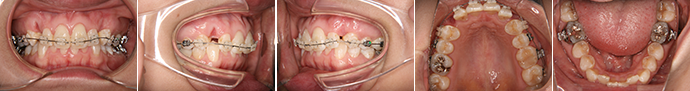

| 主訴 | 前歯が出ている |

| 年齢・性別 | 35歳 / 女性 |

| 治療方針 | 叢生も前歯の突出も大きいケース。小臼歯抜歯だけでは改善できないため、大臼歯の抜歯も行なった。 |

| 抜歯部位 | 上下顎左右小臼歯、左上第1大臼歯(計5本) |

| 使用装置 | マルチブラケット装置 |

| 治療期間 | 36か月 |

| リテーナー | 上顎インビジブル、フィックス、下顎インビジブル |

| 費用 | 885,000円(税別) |